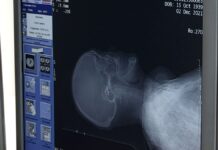

По данным врачей, пациент получил серьезные травмы и сутки провел в реанимации. Медики оценивают его состояние как тяжелой степени. С пострадавшим работают токсикологи, травматологи и психотерапевты.

«На скорой помощи в тяжелом состоянии его доставили в нашу больницу 8 марта в 1:50 ночи. Врачи скорой помощи сказали, что он был в алкогольном опьянении и прыгал с высоты шести метров. У него черепно-мозговая травма, сотрясение головного мозга, закрытый перелом поясничного отдела, позвоночника и закрытый перелом костей правой голени. Он был в реанимации целый день, сегодня его перевели в политравматологическое отделение. Сейчас он получает противошоковую терапию и в целом симптоматическое лечение».